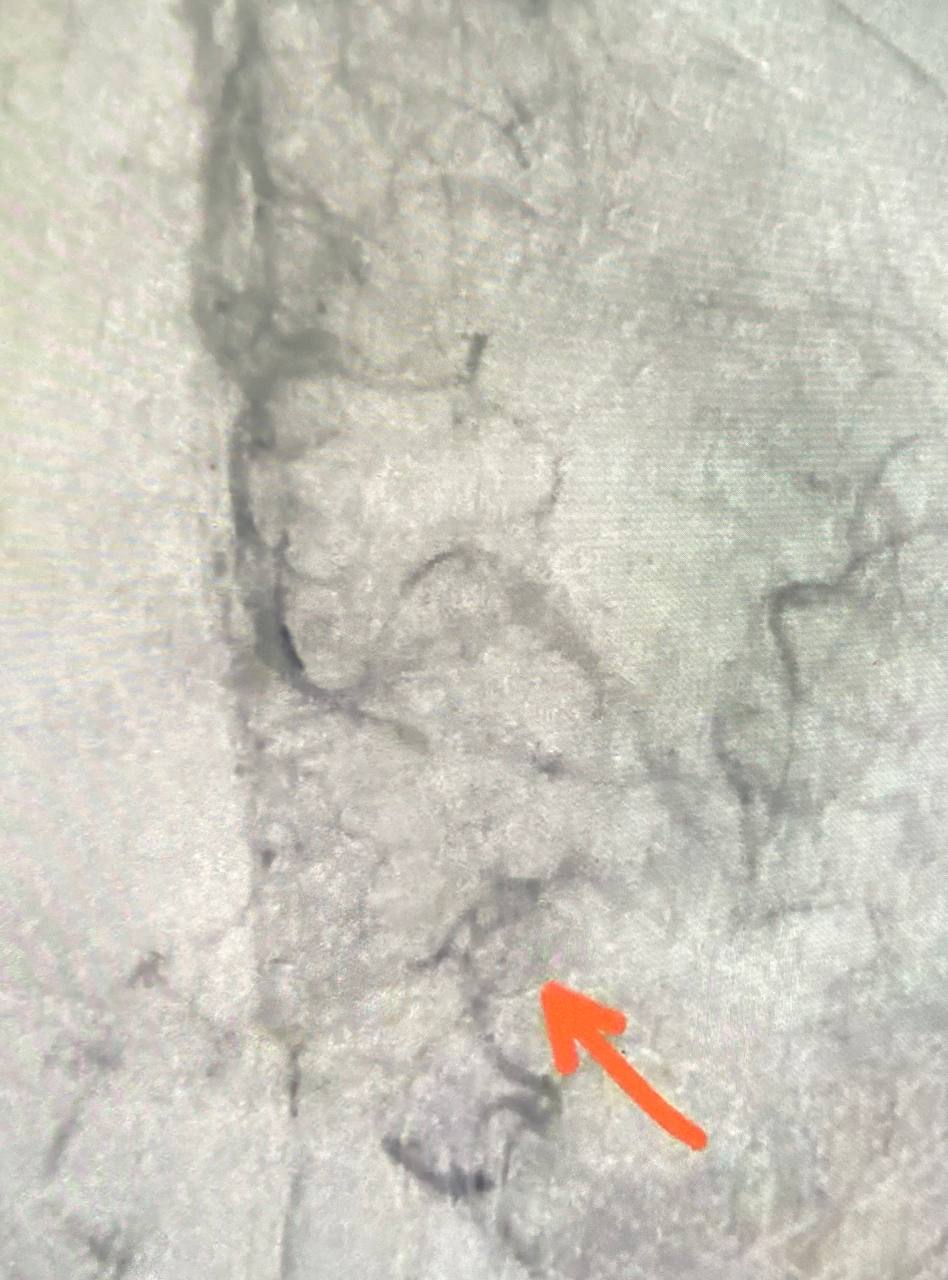

Врачи Областной клинической больницы провели тромболитическую терапию и удалили тромб из мозговой артерии (тромбэкстракция).

Уже на операционном столе пациентка начала реагировать на действия медиков - кивала головой на обращенную к ней речь, — рассказал врач-рентгенохирург отделения РХМДиЛ Александр Семенов.